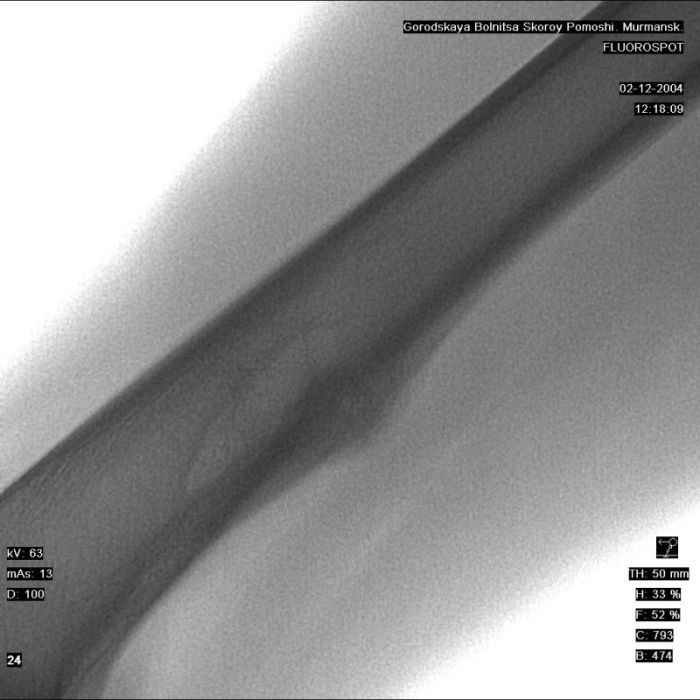

Здравствуйте, уважаемые коллеги!Представляю вашему вниманию интересный случай и пока что непонятный для меня в диагностическом плане. На днях в наше отделение (детской ортопедии и травматологии) поступил 13-летний мальчик по направлению из поликлиники с диагнозом: остеома нижней трети правого бедра.

Анамнез практически никакой: в следствие травмы (растяжение связок коленного сустава) от 07.11.2004 выполнены Rg-граммы в травмпункте и обнаружено опухолевидное образование. Первичные Rg-граммы я не публикую, так как они заметно худшего качества, да и динамики за прошедшие три недели не отражают. Болевой синдром купирован в течение трёх дней. В настоящий момент мальчика ничего не беспокоит. Ходьба не нарушена, опухоль пальпируется с трудом по задней поверхности в н\3 правого бедра, пальпация безболезненна, объем движений в суставах правой нижней конечности полный и симметричный. Кожа над опухолью не изменена.В нашей клинике проведено дополнительное обследование: общие анализы крови и мочи, биохимия крови без особенностей. Выполнены Rg-граммы на цифровом Siemens обычные и продольные томограммы срезами 3-5 мм, а также компьютерная томография поперечными срезами по 5 мм. Прошу обратить внимание, что на приведённых томограммах видны две полости 10х15 мм и 15х60 мм. Также имеются два опухолевидных образований наслаивающихся друг на друга: уплощённое и вытянутое 10х100 мм и элипсовидной формы 15х30 мм. Это хорошо заметно на фото a_1.jpg c_1.jpg и d_1.jpg. Плотность внутри полостей 125% от плотности костномозгового канала, плотность наружного опухолевидного образования 55% от плотности кортикального слоя. Также отмечается линия перелома по центру наружного опухолевидного образования.Исходя из полученных данных мнения в плане диагноза несколько разделились от 1)сочетания кортикальной фиброзной дисплазии и латентно протекавшего маршевого перелома н\3 правого бедра до 2)остеосаркомы. В отношении первого варианта не сходится отсутствие клиники при переломе такой крупной кости как бедро, второй вариант вообще оставлю без комментария, ибо некомпетентен. Хотелось бы услышать мнения коллег, с удовольствием ознакомлюсь с любыми предположениями и замечаниями.С уважением, Александр Е. КлоковОтделение детской ортопедии и травматологииБСМП г. Мурманска.